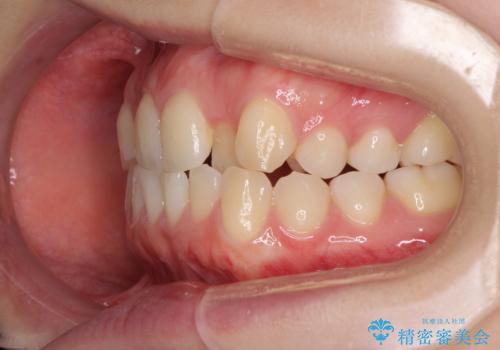

前歯のクロスバイトをインビザライン矯正で改善

- 前歯のデコボコと上下のクロスバイトを気にして来院された患者様です。

インビザラインを用い、IPR(歯と歯の間を削る)と歯列全体を拡大させることで、歯並びを整えていくこととしました。

上の前歯が下の前歯を乗り越える際、奥歯がほとんど咬めない時期があり、乗り越えた後も、インビザライン特有の奥歯の咬みにくさが続きました。

咬み合わせ改善のために治療期間を要しましたが、最終的に奥歯はしっかりと咬めるようになりました。